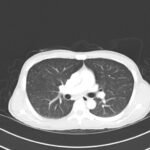

This is a case report of an HIV-positive patient with miliary tuberculosis (MTB). He presents to the emergency department (ED) two-weeks following the initiation of antiretroviral therapy (ART) with worsening cough, fevers, and malaise. The patient was diagnosed with Tuberculosis-Immune Reconstitution Inflammatory Syndrome (TB-IRIS) and subsequently treated with corticosteroids, resulting in clinical improvement over a two-week in-patient hospitalization. This case report details a rare case of TB-IRIS, a clinical diagnosis without universally agreed upon criteria. It also demonstrates a classic miliary pattern of disseminated tuberculosis on chest radiography.